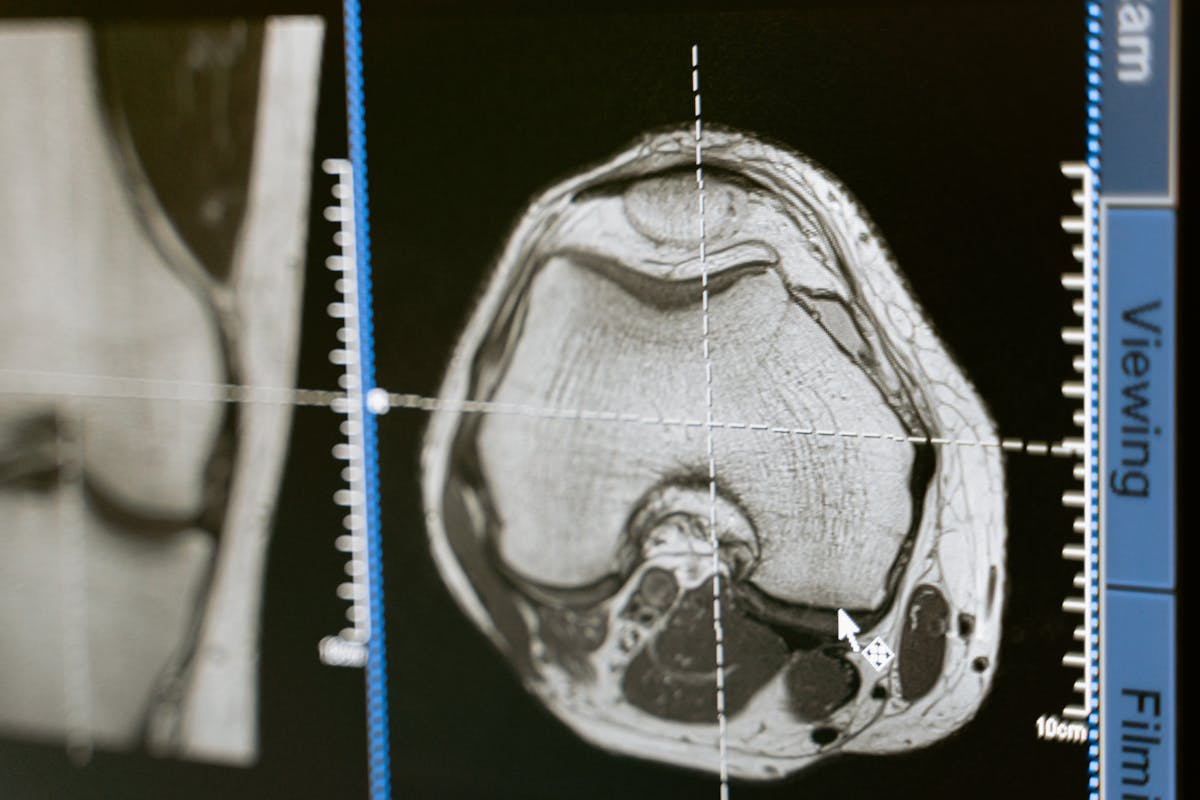

Pacijenti sa simptomima udara moraju što pre na CT ili MRI snimanje mozga – to omogućava razlikovanje ishemijskog i hemoragijskog udara u roku od 15 minuta od dolaska u bolnicu.